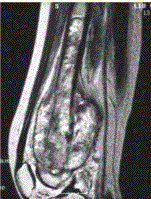

问题 患者男,16岁,左大腿下部疼痛伴肿胀2个月,逐渐加重。自感左膝上方胀痛,尤以夜间为著,伴行走困难。既往史及家族史无特殊。查体:左大腿下部明显肿胀,皮温较对侧升高。碱性磷酸酶明显增高。股骨平片及MRI见下图。 关于此病变的定位,正确的是

选项 A.病变主体位于左股骨下端骨骺,累及干骺端 B.病变主体位于左股骨下端干骺端,累及骨骺 C.病变主体位于左股骨远侧骨端 D.病变主体位于左股骨下端周围软组织,骨质受累 E.病变主体位于骨髓质,皮质受累 F.病变主体位于骨皮质,髓质受累

答案 BE